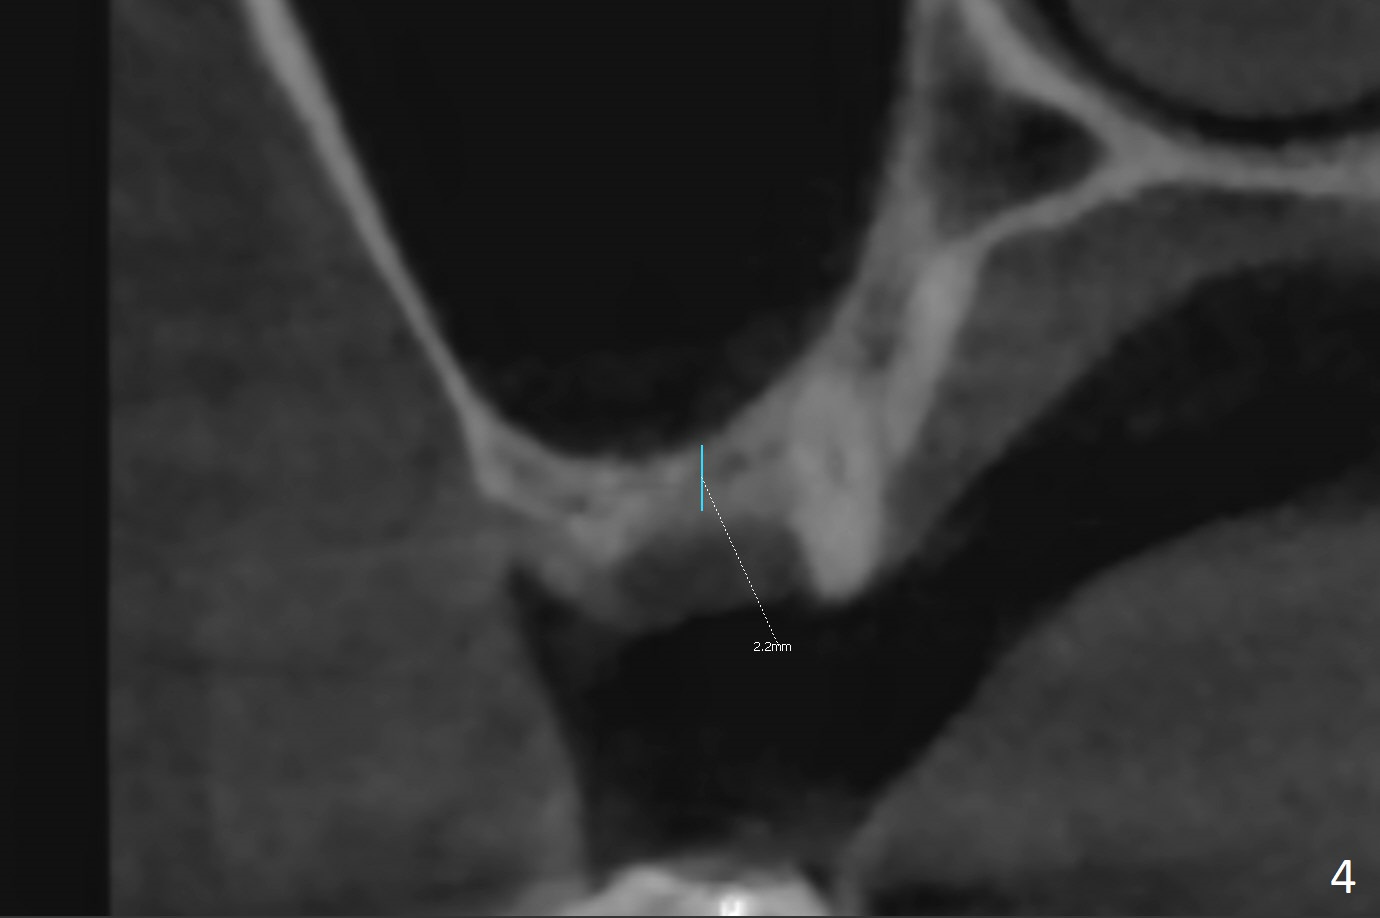

A 36-year-old woman is nervous about dentistry. She will take Valium by herselft before surgery (Fig.1). The tooth #3 has 3 residual roots (Fig.2 (CBCT 3 D occlusal view)). The bone is 2-3 mm thick (Fig.3,4 (sagittal, coronal sections)). A 5x7.3 mm implant will be placed with IS guide (Fig.5 (12 mm offset)). Since IBS implants are able to achieve amazing stability in the thin bone, prepare the shortest 4-5 mm in diameter dummy implants (IS (better surface treatment) and IBS) after sinus lift using UF Guided Sinus Lift Approach Kit (surgery). With intact tooth structure at #14, the bone height is not much (Fig.6), congenital (genetic) in nature. The infection at #31 is more severe (Fig.7). Extraction will be the 2nd in order. Because of limited bone, it is better to do bone graft first. The patient is concerned about the discolored upper right canine, which should be associated with orthodontics 20 years ago (take photos). The apical canal is obliterated (Fig.8,9 arrow) with periapical radiolucency (arrowhead). In fact the bone at #31 is so little that the tooth will be extracted for socket preservation.